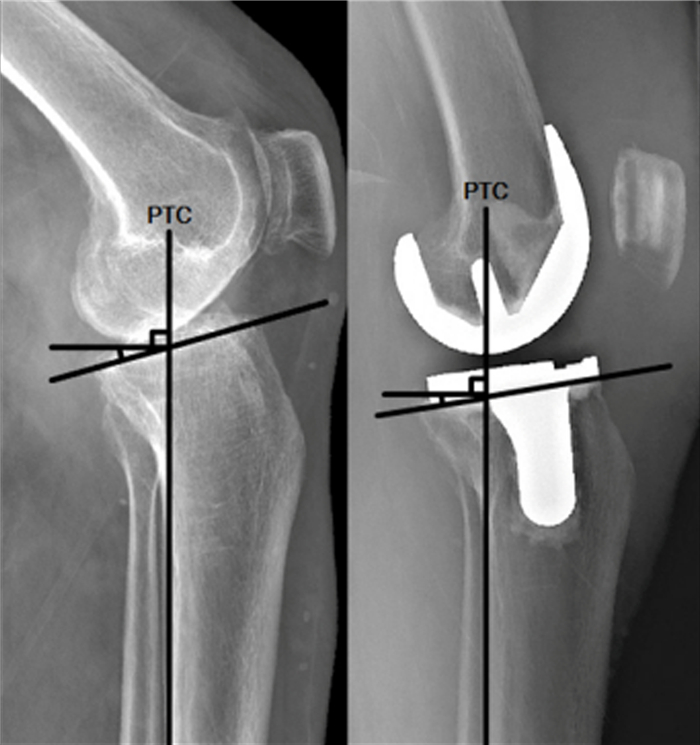

术后6周病人门诊复查指导康复锻炼,术后4个月再次门诊复查采集相关数据。检测指标包括BMI,术前及术后4个月KSS评分、膝关节ROM、胫骨平台PSA。病人术前、术后行负重位置膝关节正侧位X线检查,保证侧位X线片股骨内外髁重叠,分别应用3种方法测量胫骨平台PSA:①胫骨平台前后缘连线与胫骨中上段前侧骨皮质切线的垂线的夹角(图 1方法1);②胫骨平台前后缘连线胫骨中上段轴线的垂线的夹角(图 1方法2);③胫骨平台前后缘连线与胫骨后侧皮质切线的垂线的交角(图 1方法3)。ROM测量时病人取仰卧位,应用量角器测量。

图 1 胫骨平台PSA测量

术前、术后胫骨平台PSA(采用方法3所测得角度)见图 2。将病人根据PSA分为PSA≤5°组(n=13)、5°<PSA≤7°组(n=18)、PSA>7°组(n=9),3组术后与术前膝关节ROM差值分别为(10.74±3.58)°、(30.95±10.36)°、(35.07±7.37)°,3组比较差异有显著性(F=32.16,P<0.05)。

PTC为胫骨后侧皮质切线,斜线为胫骨平台前后缘连线,PTC垂线与斜线的夹角就是测量的角度,未安装假体为术前,安装假体为术后。 图 2 方法3测量胫骨平台PSA